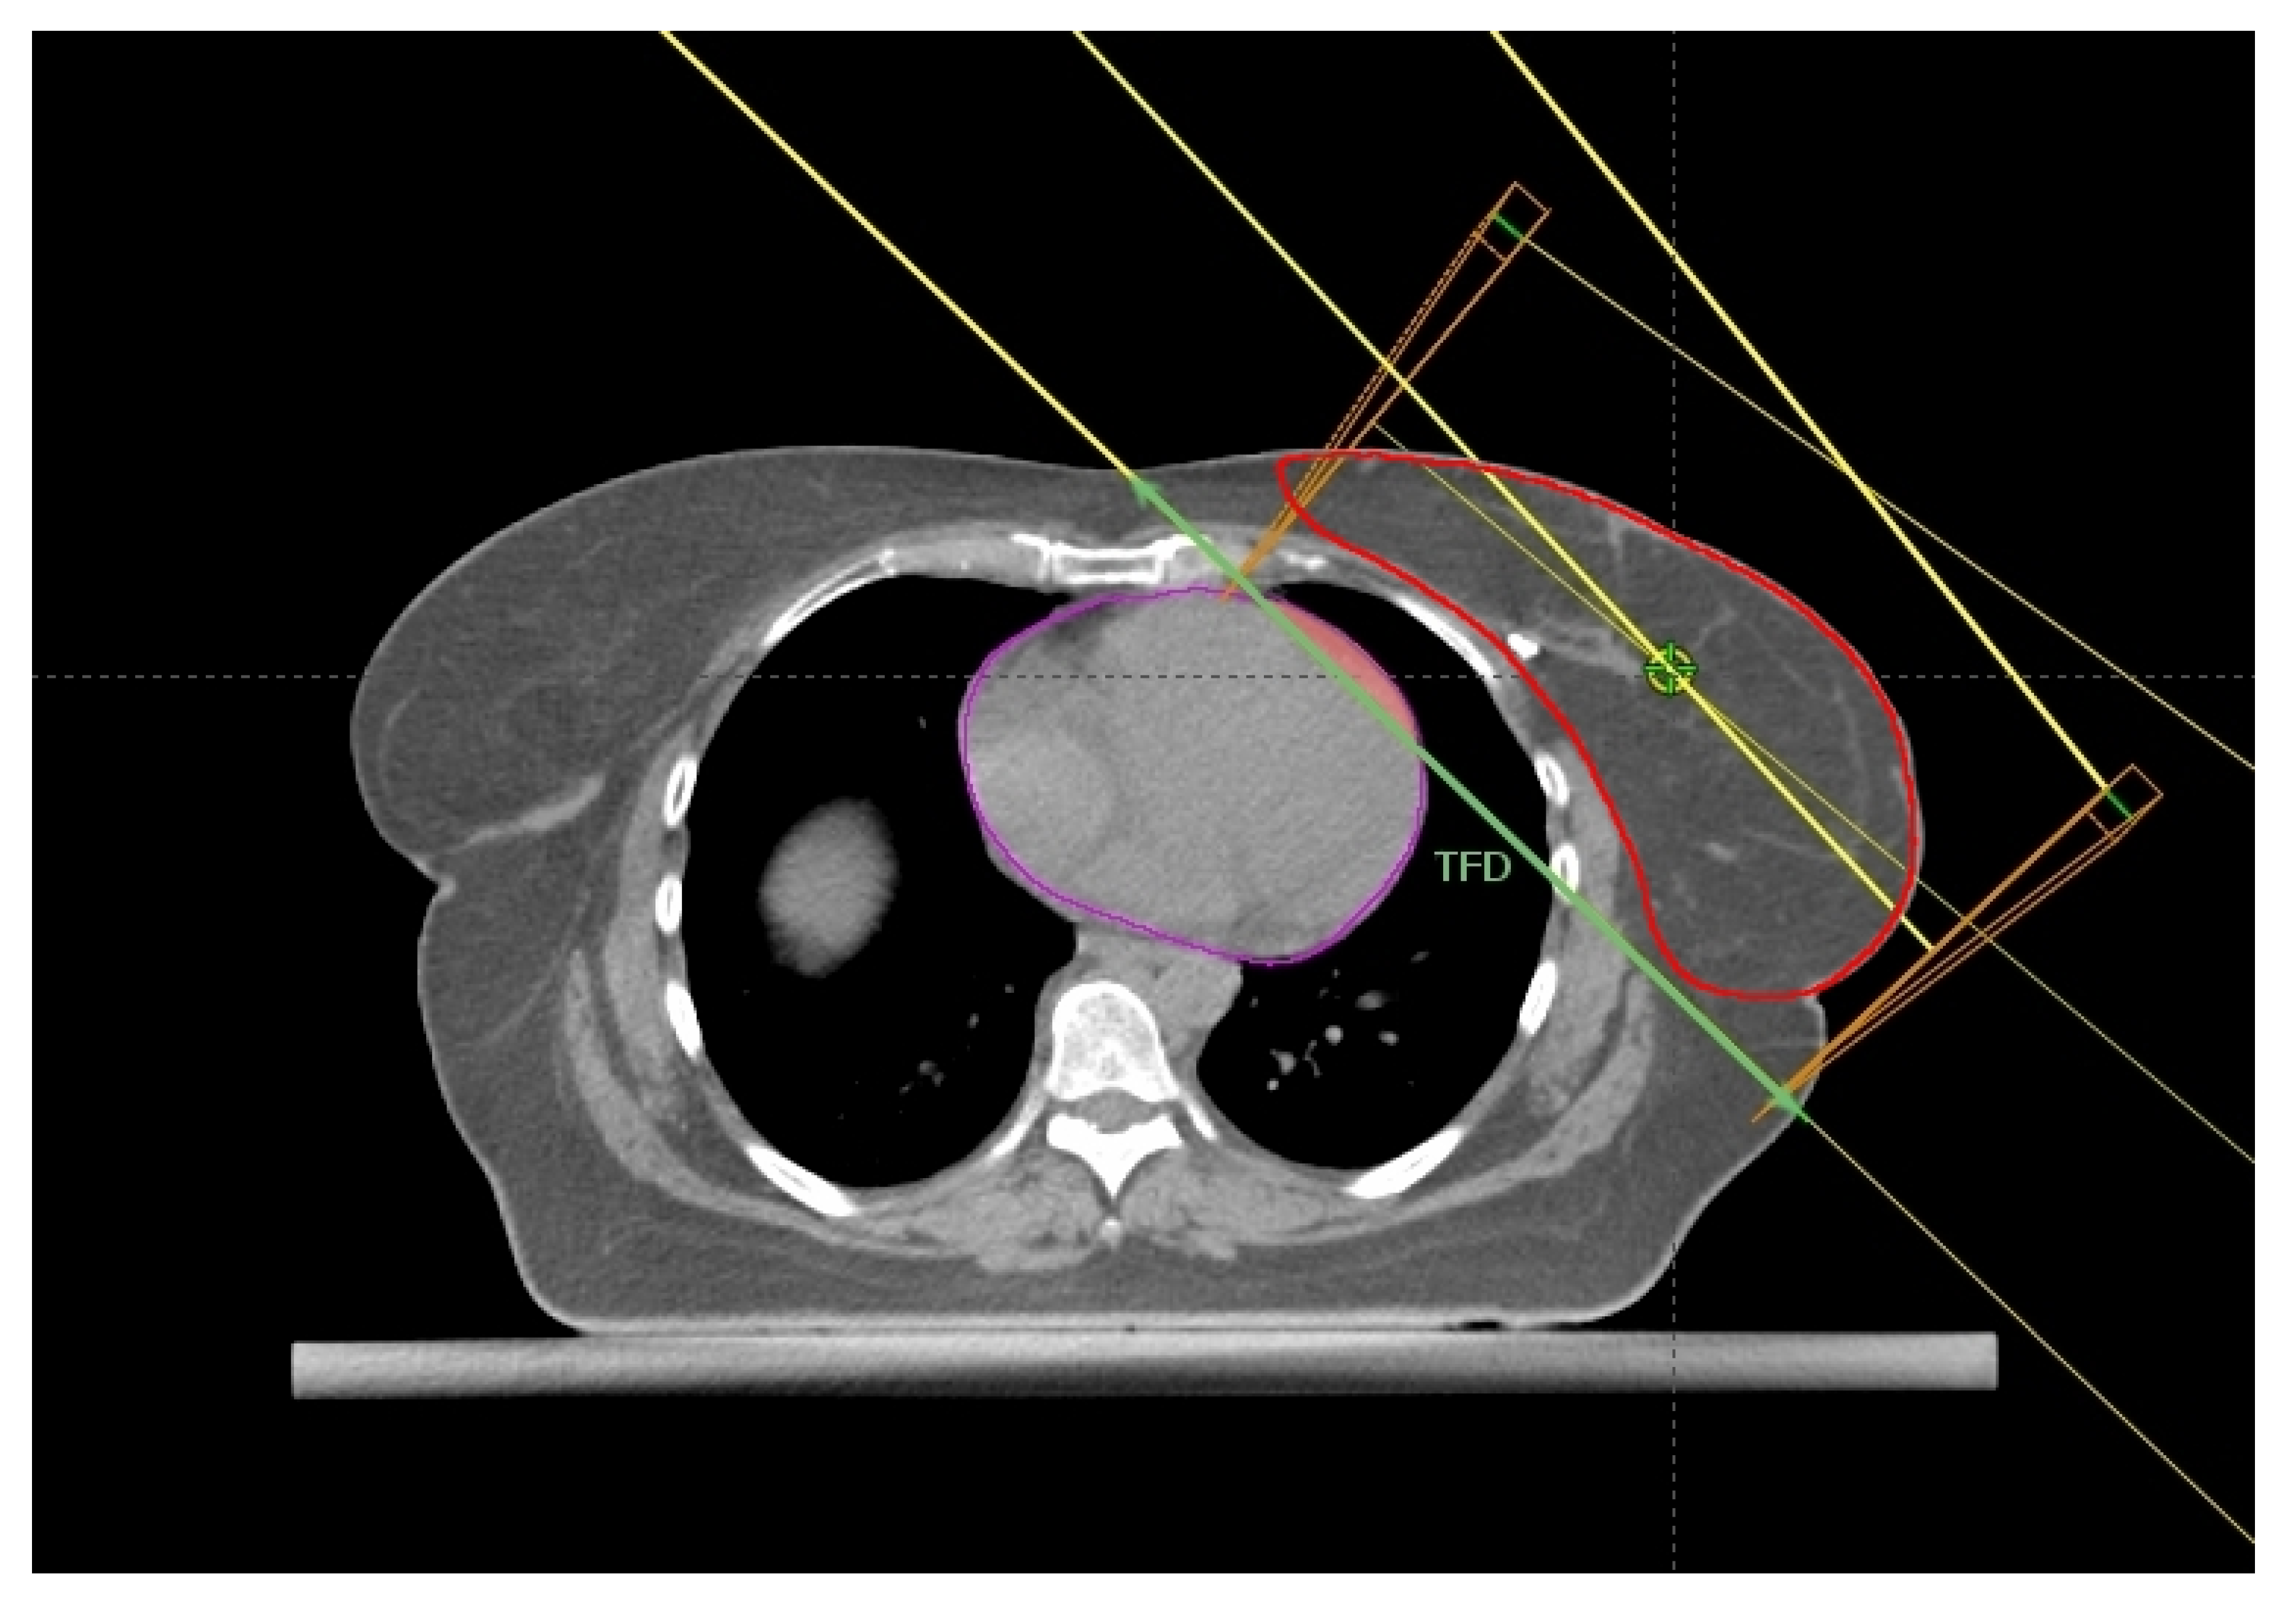

2.1. Breast Size and Chest Wall Separation